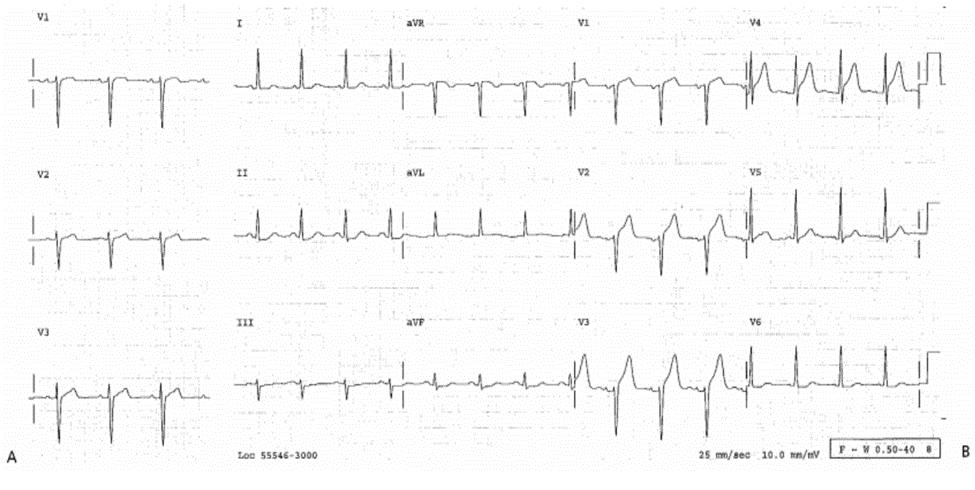

ECG 9-1A (Type 3)

Ghi lúc 03:21.

■ Không đặc hiệu, sóng R chậm tiến triển. Bệnh nhân vẫn còn đau ngực. Bà được nhập vào CCU trước khi các chuỗi ECG được ghi lại.

ECG 9-1B (Type 1b)

Ghi lúc 05:52.

■ ST chênh : V1 – V3 (1mm ở điểm J nhưng 2 mm tại 80 ms sau điểm J); và sóng T cao cấp tính: V2—V5, xác định là mới. Chỉ có ECG này cũng chẩn đoán được AMI nhưng đặc biệt rõ hơn khi so sánh với ECG 9-la.

Diễn biến lâm sàng

Mặc dù máy tính đọc ECG này là “cân nhắc nhồi máu cơ tim thành trước,” nhưng bác sỹ lâm sàng giải thích ECG 9-lb là bình thường. AMI thành trước được thấy rõ ở ECG sau đó, và tắc 100% đoạn xa LAD và đã được tái thông bằng nong mạch lúc 12:00 giờ. CK toàn phần đạt đỉnh 700 IU/L 20 giờ sau khi biểu hiện triệu chứng, cTnI = 6.8 ng/mL.

Kết Luận

Chụp mạch ngay lấp tức ± PCI được chỉ định.

Case 9-5

AMI Thành Trước Khó Phát Hiện (tiếp)

ECG 9-5B (Type 3)

ECG ghi được trước đó, chỉ có V1—V6.

■ ST đẳng điện lúc bình thường. So sánh với ECG trước đó giúp cho bác sỹ chẩn đoán xác định ECG 9 – 5A chẩn đoán AMI thành trước.

Tiêu huyết khối đã được sử dụng. Ghi ECG sau liệu pháp tái tưới máu biểu hiện tương tự như ECG 9-5B (ECG bình thường), không có sóng Q và sóng T bình thường ở V2. Troponin (cTnI) và CK toàn phần có thể xác định nhưng tăng lên nhẹ. Siêu âm tim không có WMA và chức năng thất trái bình thường.

Khi điều trị nhanh AMI thì chỉ có một lượng nhỏ cơ tim bị tổn thương, do dó không có bất thường tái cực kéo dài như sóng T đảo. Chẩn đoán và điều trị đúng lúc trong Case này được làm dễ hơn bằng nhận biết các dấu hiệu nghi ngờ AMI và so sánh với ECG trước đó.